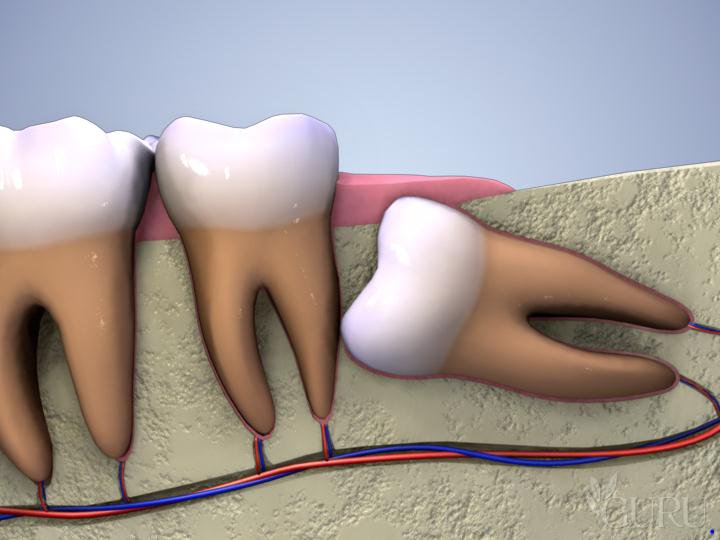

- Ngoài ra, sự xuất hiện của sâu răng hàm là một hiện tượng xấu. Nó cũng có thể ảnh hưởng đến sự phát triển của các răng vĩnh viễn. Nếu răng sữa bị sâu và không được điều trị, có thể gây ra vấn đề cho sự phát triển. Thậm chí ảnh hưởng vị trí của răng vĩnh viễn sau này.

Nhổ răng sữa quá sớm có thể ảnh hưởng đến sự phát triển của xương hàm. Điều này gây lệch lạc vị trí răng vĩnh viễn do mất khoảng trống mọc răng. Thậm chí làm hẹp cung hàm. Trong các trường hợp này, bác sĩ sẽ cân nhắc kỹ lưỡng. Sau đó sẽ chỉ định nhổ răng khi thực sự cần thiết. Thông qua đó đảm bảo sức khỏe răng miệng lâu dài cho trẻ.

- Răng đã chết tủy hoàn toàn, không còn khả năng hồi phục. Thậm chí có nguy cơ lây nhiễm sang mầm răng vĩnh viễn.

- Răng sâu ở mức độ nặng, không đáp ứng điều trị bằng các phương pháp bảo tồn. Tiềm ẩn nguy cơ lây nhiễm sang các răng sữa hoặc mầm răng kế cận.